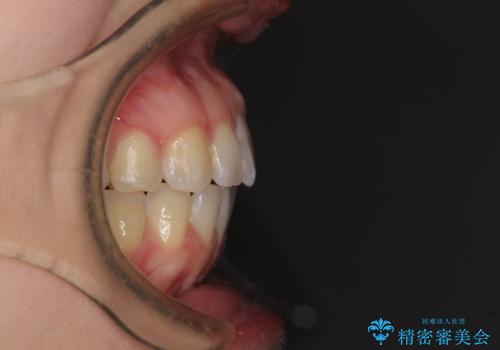

気になる上の歯を改善 インビザライン矯正

- 矯正治療の後戻りが気になるとのことで来院された患者様です。

上顎の後戻りをインビザライン・ライトで治療することとしました。

上顎のみの治療を希望されたため、咬み合わせをしっかりと改善することはできませんでしたが、審美面が大きく改善され、日常生活の機能面でも不具合を感じることはなく、大変満足していただきました。